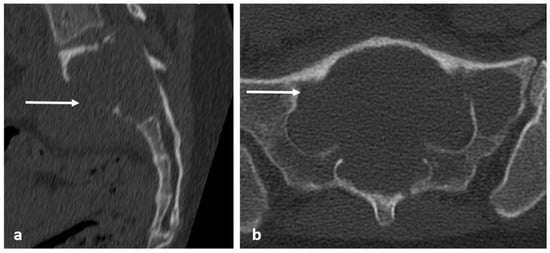

| Osteoma | Dense sclerotic lesion. Hounsfield density >885 a helpful indicator but not definitive. | T1 and T2, STIR hypointense due to sclerosis. |